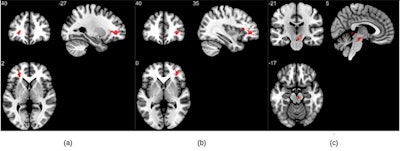

The study showed that participants who had COVID-19 and recovered had higher susceptibility values on MRI in their frontal lobes and brain stems compared to the healthy controls -- brain regions linked to fatigue, insomnia, depression, headaches, and cognitive disruptions, according to Mishra's group. The researchers also found differences in the right ventral diencephalon area of the brain stem, which coordinates the endocrine system and regulates the sleep-wake cycle, among other tasks.